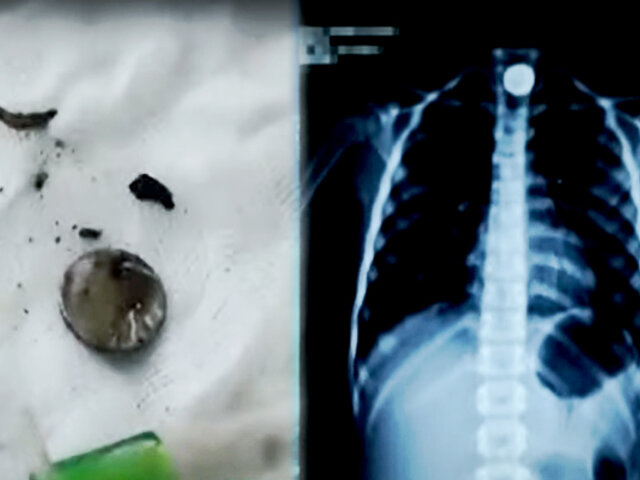

Una menor fue intervenida quirúrgicamente de emergencia, pues se le encontró un pequeño objeto ovalado dentro de su organismo. Médicos del hospital La Caleta de Chimbote salvaron la vida de la niña quien tenía una pila alojada al interior de su esófago.

Este objeto permaneció por cinco días en la menor sin que sus padres lo sospecharan. La pequeña fue sometida a una radiografía, donde se le encontró el cuerpo extraño por lo que procedieron con la intervención.

Los especialistas indicaron que los químicos que soltó la pila produjeron algunos daños en el esófago de la menor. Por medio de pinzas se extrajo el elemento extraño con mucho cuidado para no afectar a la pequeña. La madre de la paciente agradeció a los médicos por su rápida intervención.